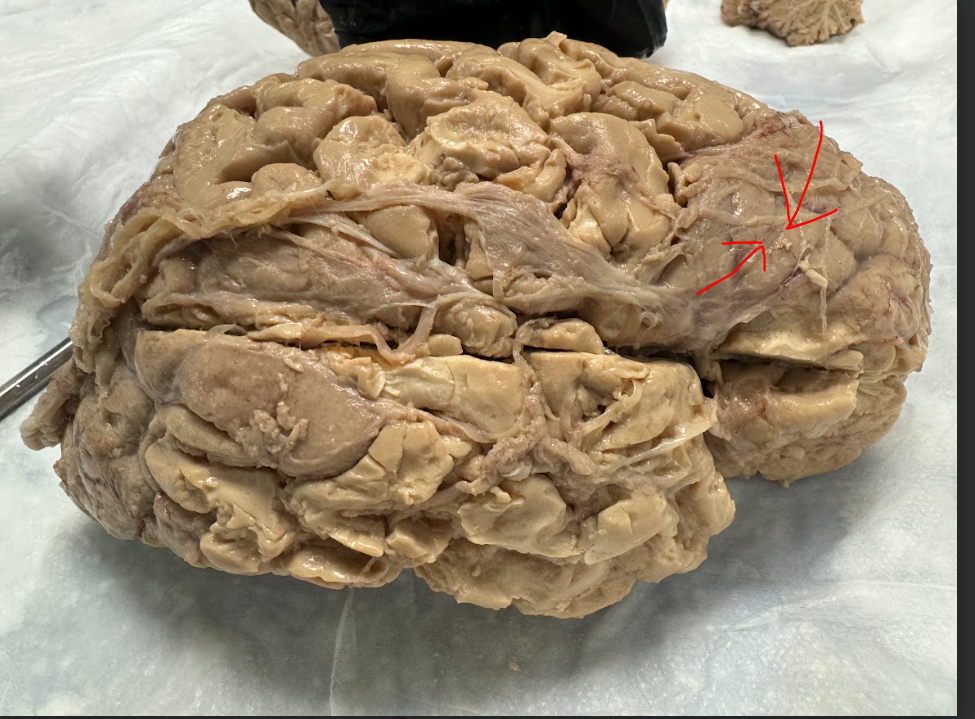

Anterior cerebral artery

Edited: Facial N